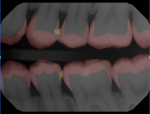

Since 2020, technological advancements have resulted in an exponential increase in the utilization of artificial intelligence in daily life, particularly in the field of dentistry. Leading dental clinicians are working with machine-learning scientists to develop and encode computer algorithms to measure and analyze radiographs, photographs, clinical assessments, and chart notes with dentist-level accuracy and understanding. This capability will result in a highly accurate output and clinically relevant results. Leading companies have developed algorithms to detect caries and periodontal disease, in addition to a wide array of clinical determinants. These algorithms and AI-enhanced software can help hygienists improve patient communication and demonstrate the necessity for treatment. The algorithms are built on millions of data points learned through rigorous clinical inputs, and are currently achieving equal to, and in some instances better than, single clinician accuracy.